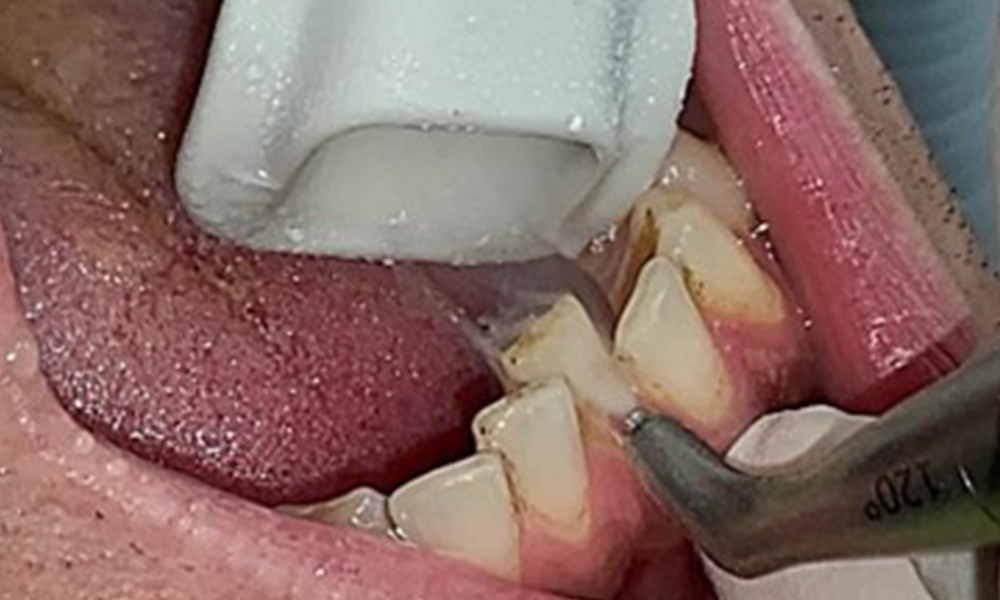

Use of a piezo-driven ultrasonic device in the lingual area near 36

Fig. 10 Use of a piezo-driven ultrasonic device in the lingual area near 36 (Proxeo Ultra, W&H, shown here), © Dr R. Krapf

The objective would be to control disease risk by removing supragingival and subgingival biofilm. The instruments can be selected based on patient needs. First, calculus and any concretions must be removed using ultrasonic and/or manual instruments (Fig. 10).